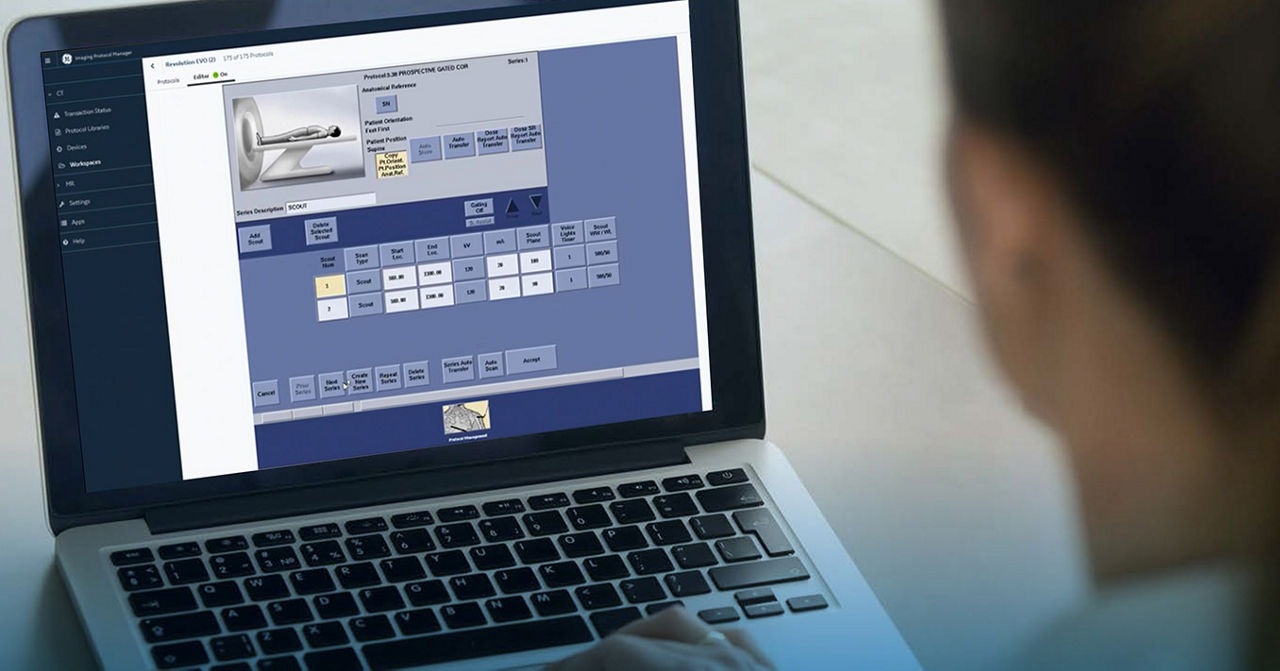

Leveraging transformational imaging technology to realize the promise of precision medicine and help deliver better outcomes. Our medical imaging products range from systems, including MRI, CT, PET, SPECT, Ultrasound, Mammography and X-ray, to digital and AI solutions to help drive healthcare digitialization, help enable faster exam workflow, improve clinical outcomes and increase efficiencies.